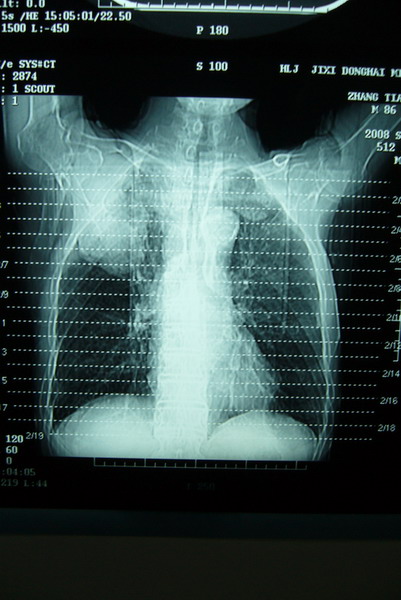

标题: CT15579:男 86岁 咳嗽 咳少量白痰 发热2天 吸烟史60年 [打印本页]

标题: CT15579:男 86岁 咳嗽 咳少量白痰 发热2天 吸烟史60年

右肺上叶巨大软组织肿块,轮廓不规则,纵隔内有肿大淋巴结,首先考虑肺癌。

右上肺一不规则团块,边缘有分叶和毛刺,纵隔有淋巴结肿大。右肺周围性肺癌首先考虑。